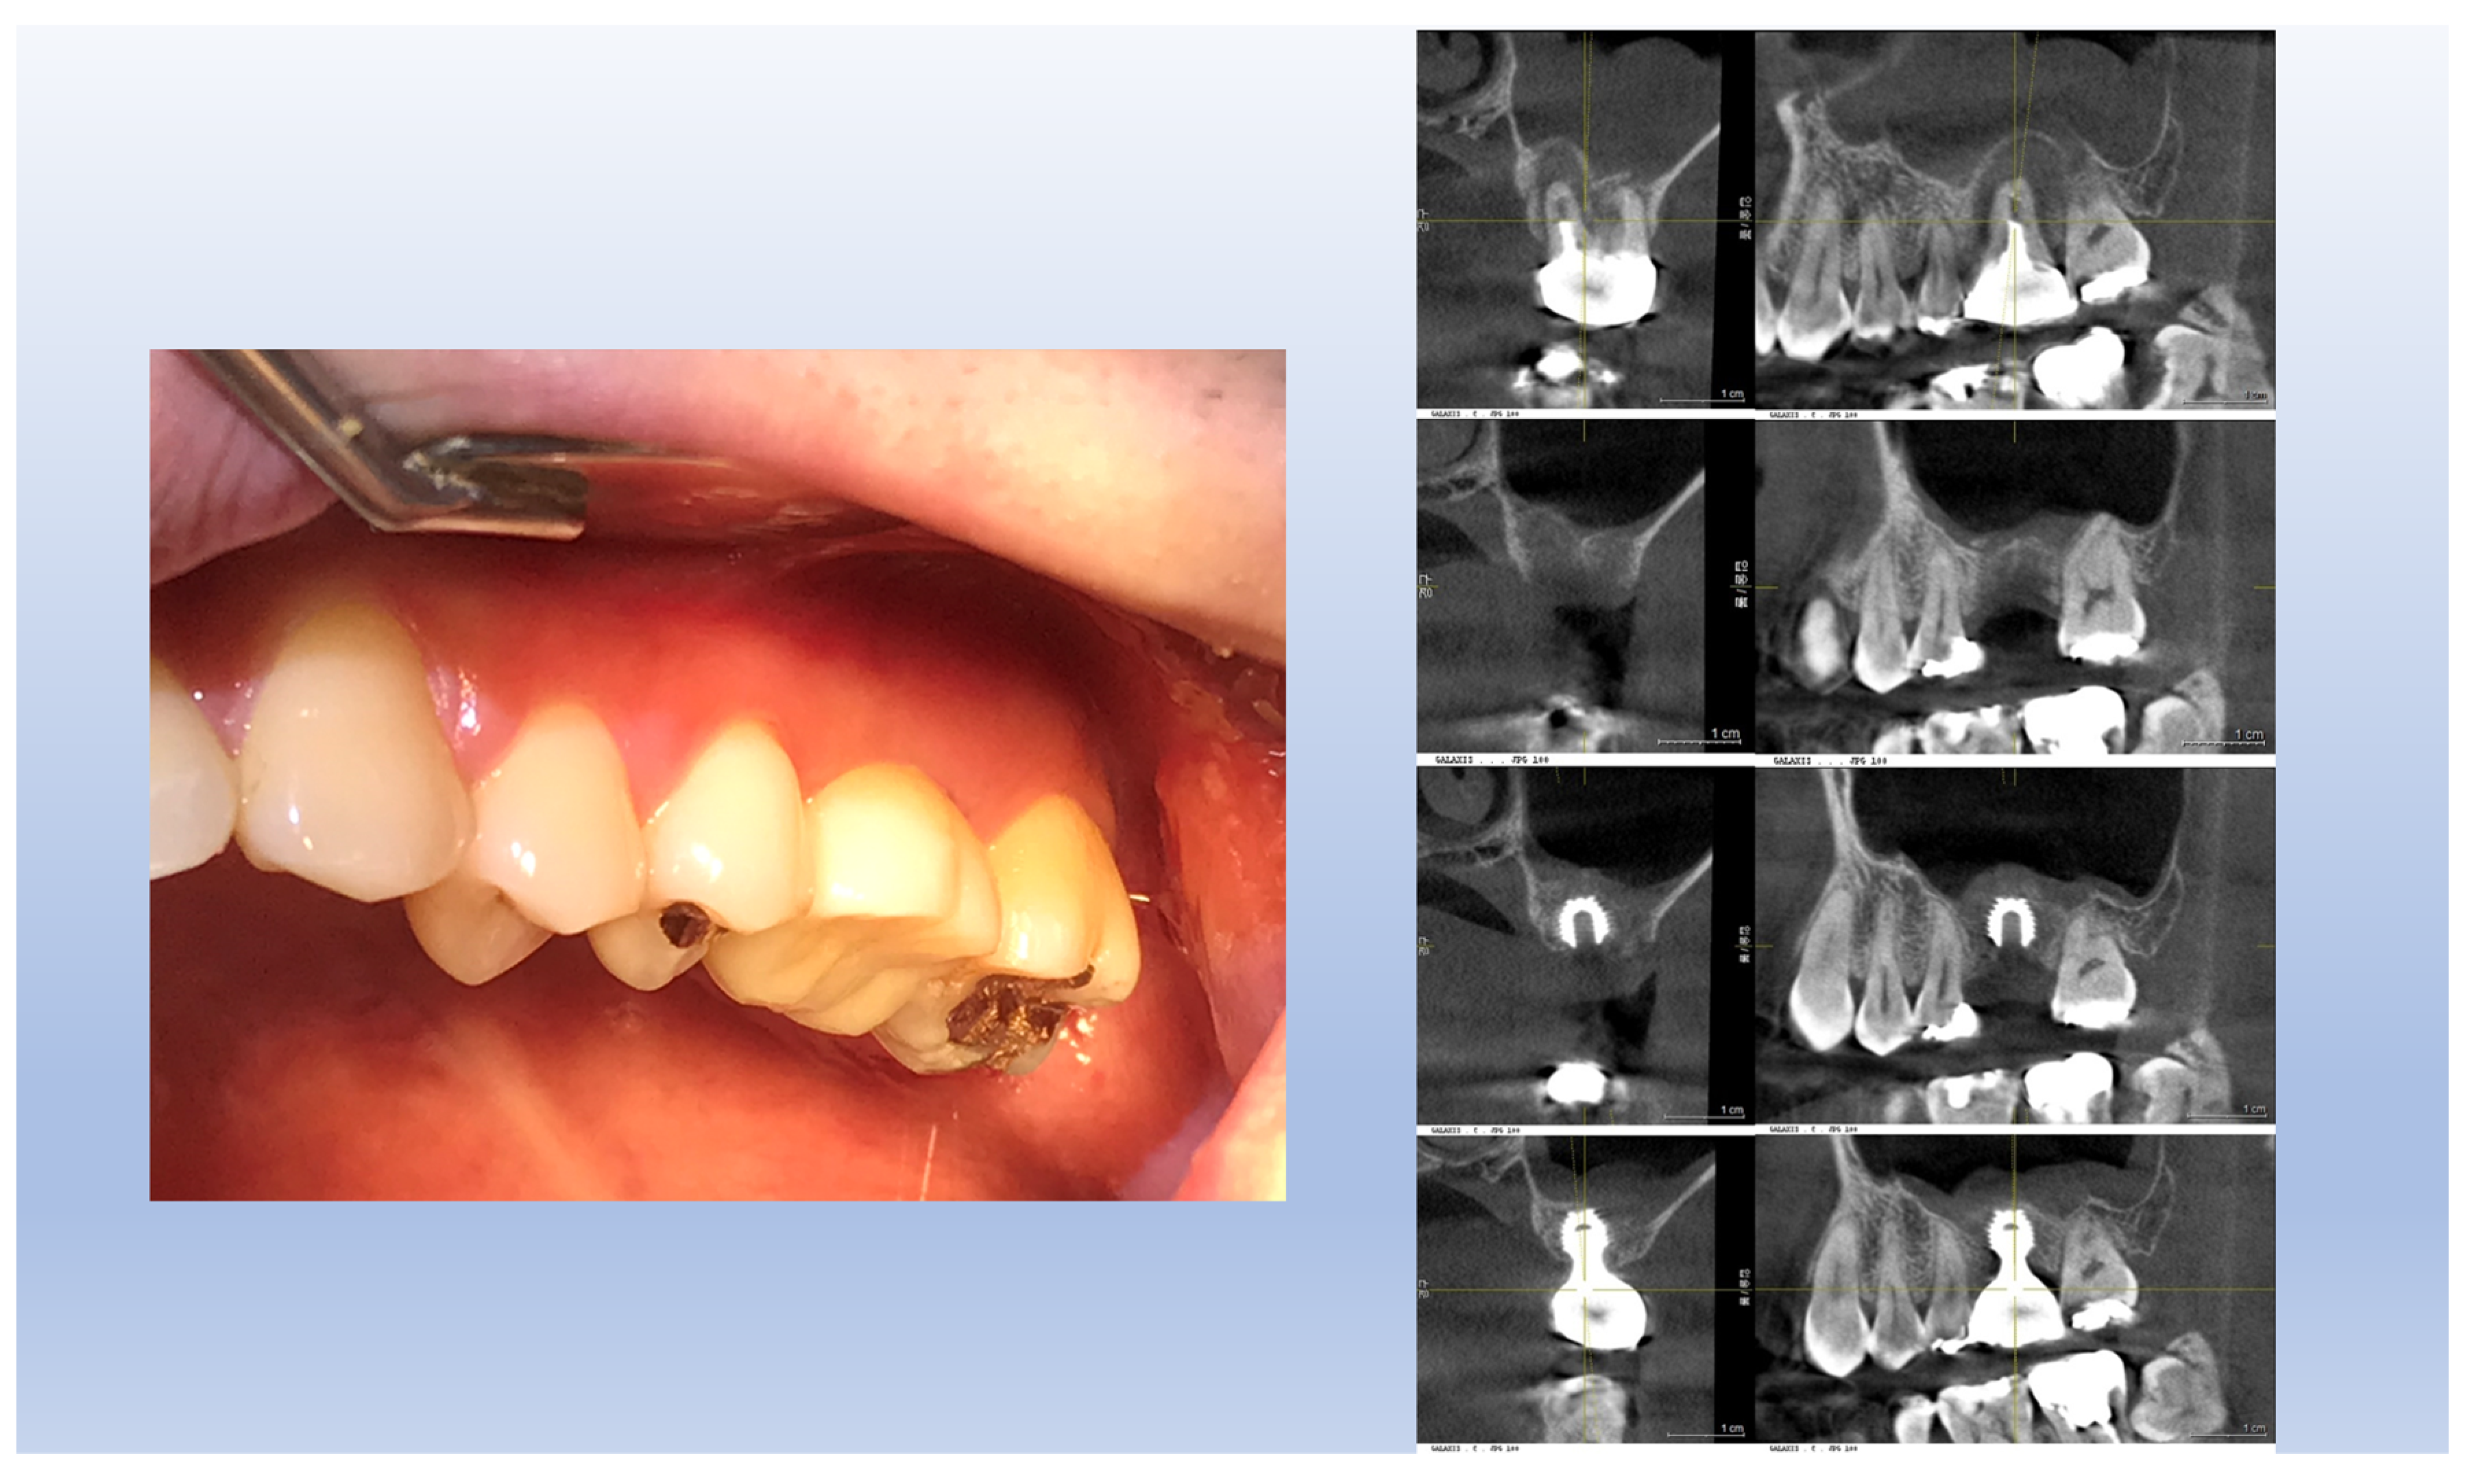

The cases examined in this study demonstrate that the area of transmucosal soft tissue, which corresponds to the junctional epithelium and connective tissue (the biologic width), around dental implants is enlarged due to deep subcrestal placement. This enlargement was quantitatively analyzed using Cone Beam Computed Tomography (CBCT). The results indicated that the average length of the Transitional Zone (TZ) was 3.8 mm, with an average thickness of 0.6 mm. These measurements suggest that the majority of the TZ is composed primarily of connective tissue. As the TZ extends toward the peripheral area and its thickness increases to more than 1.0-1.5 mm, it typically becomes covered with junctional epithelium. The predominant structure of the submucosal area is a connective tissue zone with junctional epithelium primarily present at the entrance, measuring approximately 0.5-1 mm, as detailed by Ikiru Atsuta et al.^[30].

Figure 16. Transmucosal Soft Tissue Structures in Subcrestally Placed Implants. This figure presents clinical images showcasing the transmucosal area related to the junctional epithelium and connective tissue (the biologic width) in subcrestally placed implants (SPIs), captured either after the removal or before the placement of the prosthetic parts. Compared to epi- or equi-crestal implant placements, these SPIs exhibit a larger area of transmucosal soft tissue. The right image distinctly identifies three layers: the subcrestal zone, the Transitional Zone (TZ), and the marginal zone, where the pale pink color closely matches the adjacent oral epithelium.

Figure 19. Connective Tissue Layers in Subcrestally Placed Implants. This figure illustrates the two distinct layers of connective tissue observed in subcrestally placed implants. The deeper layer, adjacent to the subcrestal bone, is a very thin, periosteum-like layer with a pale white color. The superficial layer, situated above the crestal bone, is thicker and appears red. This visual distinction highlights the varied structural composition of connective tissue in different zones around dental implants.